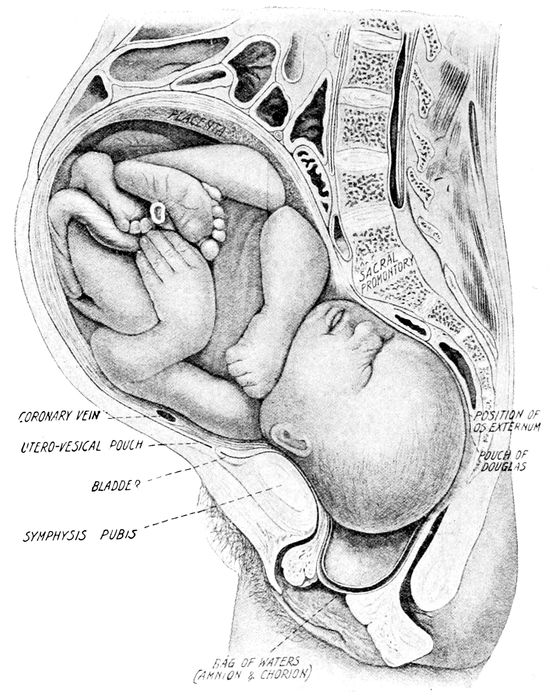

| 41. |

Child in second stage of labor |

116 |

| |